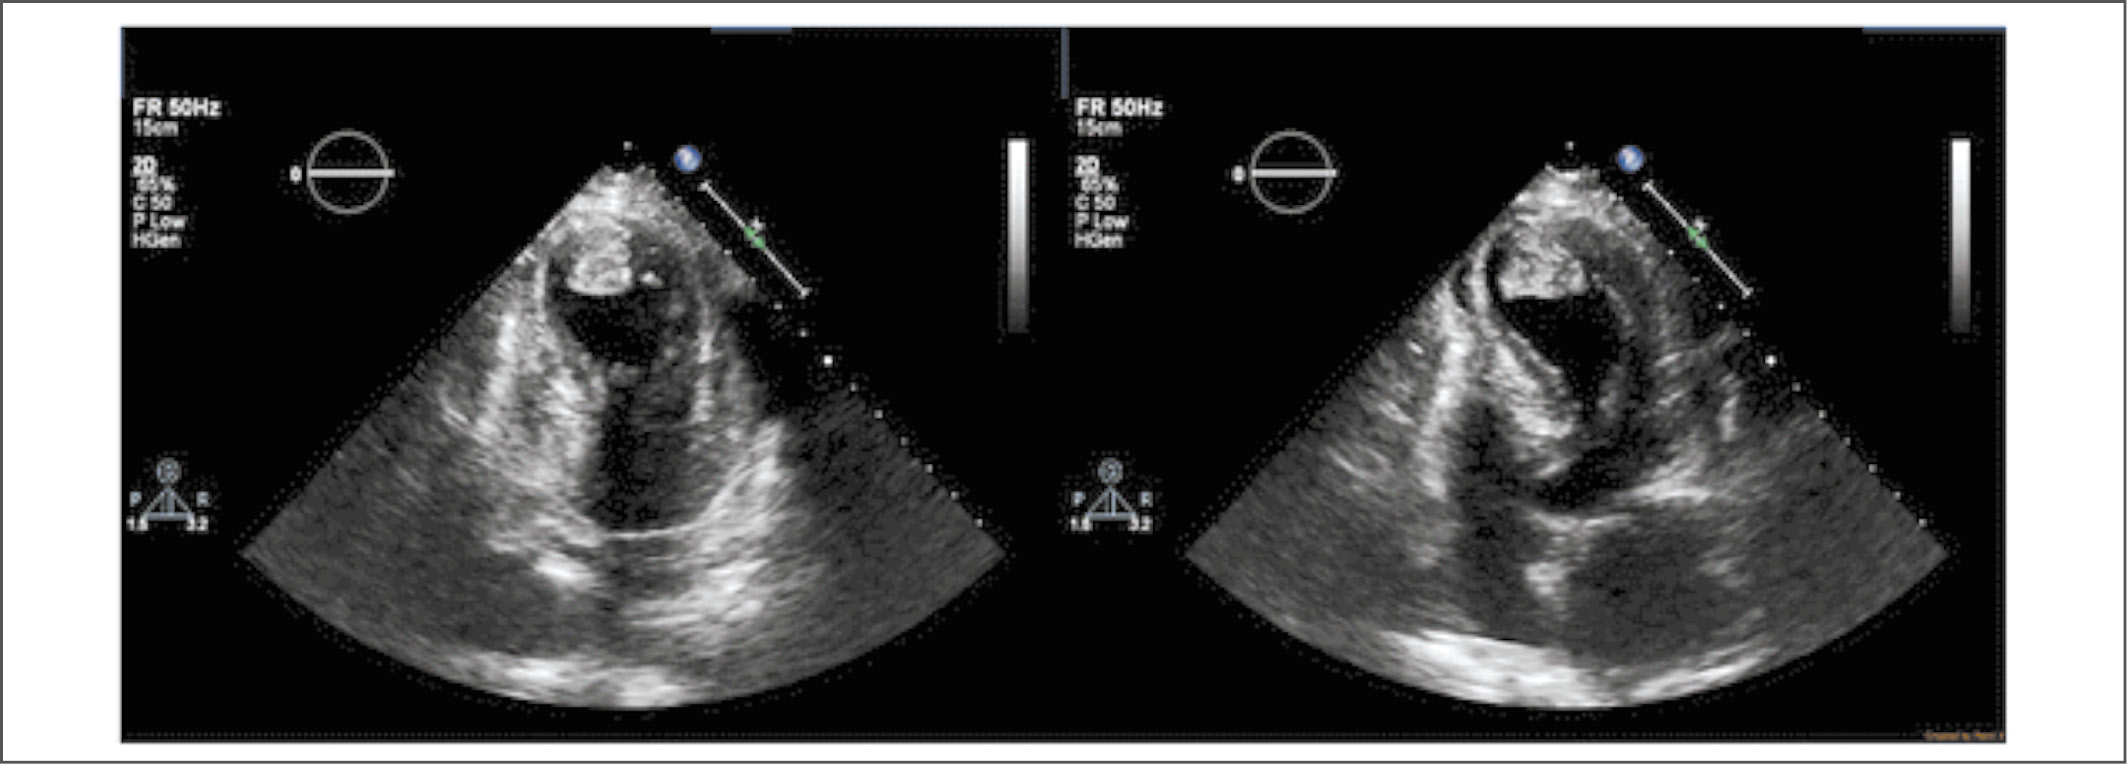

При осмотре установлено снижение АД до 80/50 мм рт. ст. На ЭКГ – картина острого, с подъёмом сегмента ST, инфаркта миокарда (рис. 6). Госпитализирована в отделение реанимации и интенсивной терапии. Больная получала тикагрелор – 180 мг, ацетилсалициловую кислоту – 100 мг, гепарин натрия – 5000 ед внутривенно (однократно). Экстренно выполнена КАГ, на которой стенозирующего атеросклеротического поражения коронарных артерий не выявлено (рис. 7). На ЭКГ от 14.05.2019 г. обнаруженные изменения расценили как инфарктоподобные. Также была выполнена ЭхоКГ (рис. 8).

Рис. 8. Систолическое баллонирование верхушки ЛЖ пациентки К. Тромб в верхушке ЛЖ.

Fig. 8. Systolic perforation of patient’s К. left ventricular apex clot at the top of the left ventricle.

ЭхоКГ от 14.05.19 г.: шарообразное расширение верхушки, частично – средних отделов сердца. Нарушения локальной сократимости миокарда: акинезия всех сегментов верхушки, частично – средних, переднего, боковых, заднего, перегородочных сегментов ЛЖ. Глобальная систолическая функция ЛЖ снижена: ФВ ЛЖ – 45% по Симпсону.